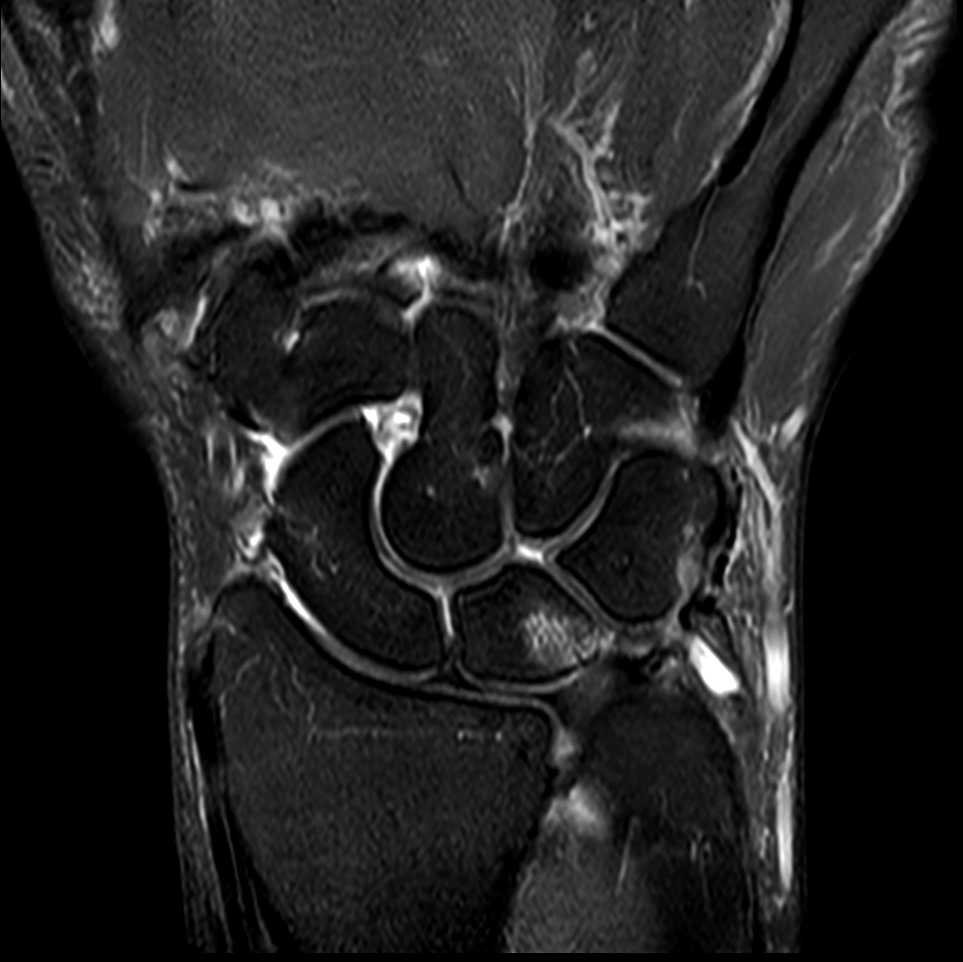

Comprehensive wrist imaging